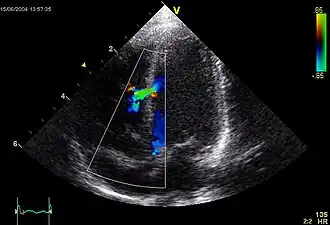

Ventrikelseptumdefect of VSD is een aangeboren hartafwijking waarbij er een gaatje aanwezig is in het tussenschot (het septum) van de twee ventrikels (hartkamers). Door dit defect is uitwisseling van bloed tussen de beide ventrikels mogelijk. Doordat er in de linkerzijde van het hart een fysiologische hogere bloeddruk is dan in de rechterzijde, zal in de meeste gevallen het zuurstofrijk bloed vanuit het linker ventrikel naar het rechter ventrikel stromen. Dit wordt ook wel een links-rechtsshunt genoemd. Er is hier sprake van een volumeoverbelasting van het linker ventrikel van het hart en van de longcirculatie. Doordat er relatief meer bloed door de long stroomt kan er pulmonale hypertensie ontstaan. Als er een ernstige pulmonale hypertensie bestaat, zodat de druk in het longvaatbed boven de druk in het veneuze deel (aders) van het lichaam uitkomt zal de bloedstroom door het VSD omdraaien. Dit wordt ook wel het eisenmengersyndroom genoemd.